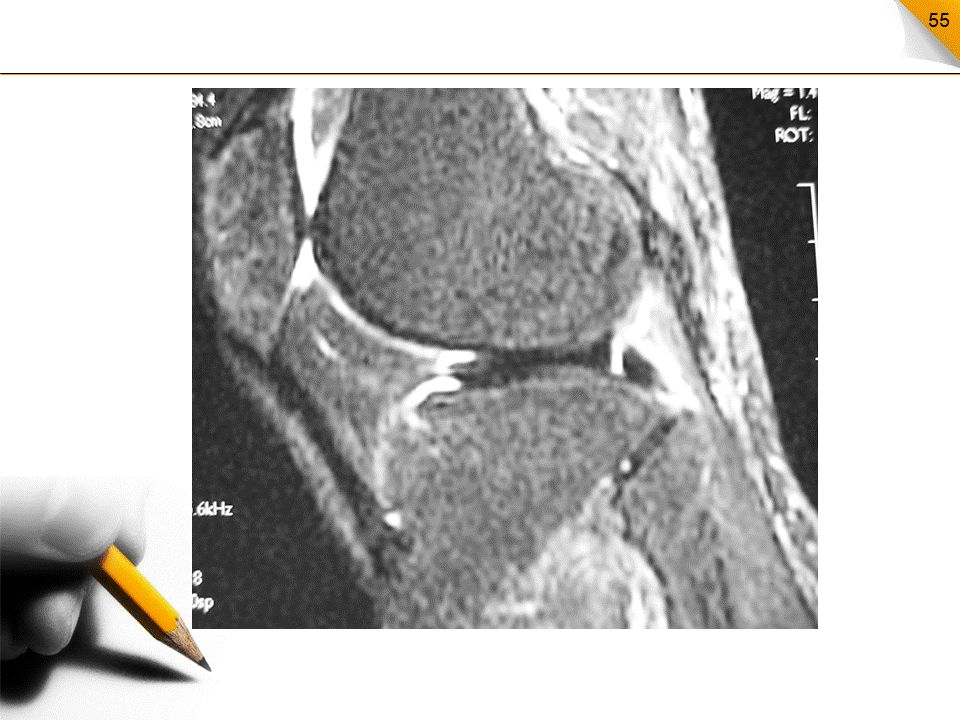

前交叉韧带撕裂MR表现

部分撕裂:局部信号增高、边缘毛糙松弛扭曲完全撕裂:连续性中断,断端毛糙呈拖把状急性撕裂:伴有关节腔积液和髌下脂肪垫水肿

前交叉韧带完全撕裂直接征象:连续性中断、韧带增粗、信号增高间接征象:PCL曲度异常、胫骨前移、股骨髁和胫骨平台的骨挫伤、半月板及侧副韧带撕裂等。